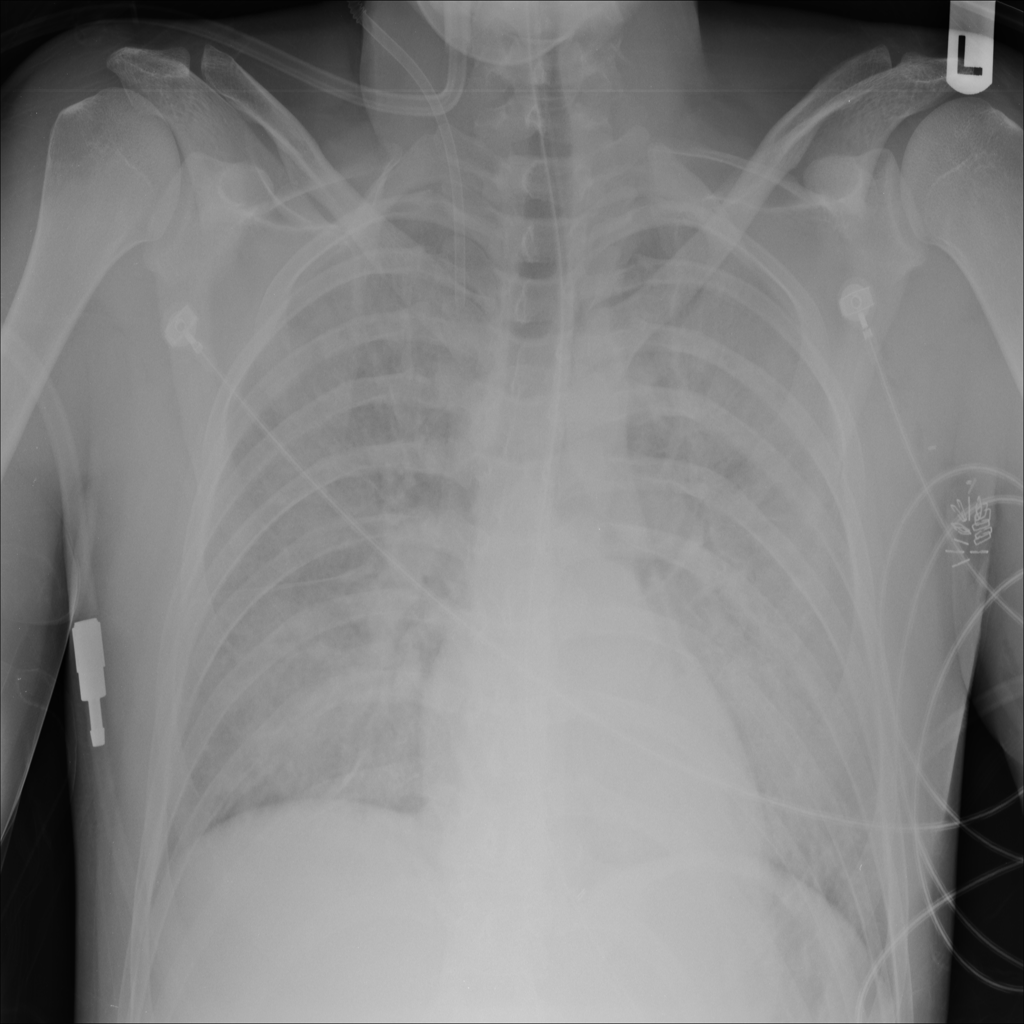

Showing up to 90 reference images for Edema.

PAT-5B86 · IMG-009Edema

PAT-5B86 · IMG-009

PA

Pulmonary edema refers to fluid accumulation within the lungs, often linked to cardiac or noncardiac causes.